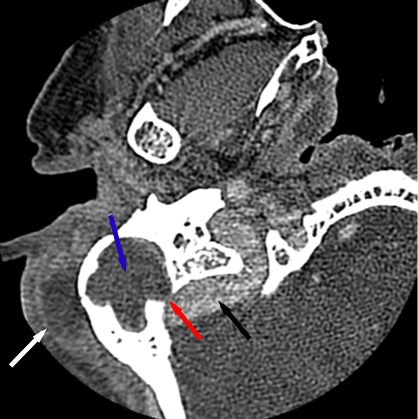

- Opacification of the right middle ear and mastoid air cells with resorption of mastoid septae

- Infection erodes through the cortex resulting in an external subperiosteal abscess

- Thinning of the posterior mastoid wall without extra-axial or intraparenchymal brain abscess

- Additional area of thinning of the right tegmen tympani

- Right sigmoid sinus remains patent

- Coalescent otomastoiditis

Findings consistent with right acute complicated coalescent otomastoiditis, including resorption of mastoid septae, adjacent external subperiosteal abscess, and thinning of the posterior mastoid wall.

No evidence of intracranial extension. The right sigmoid sinus is patent.